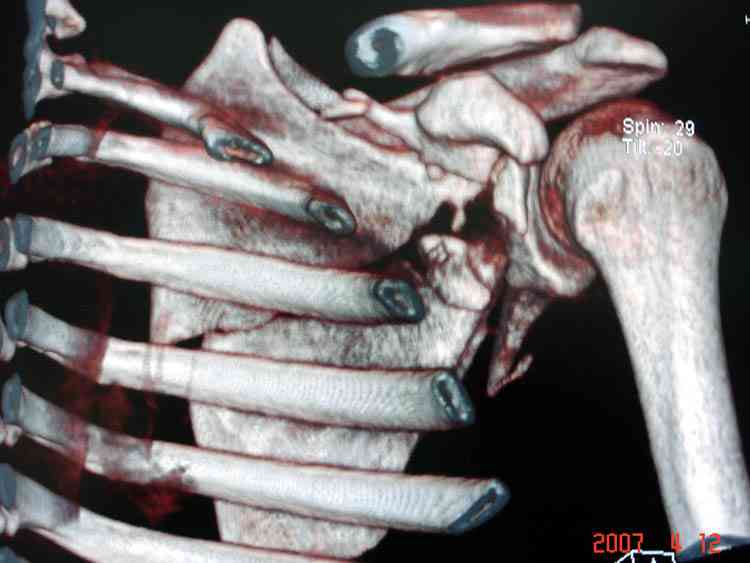

К-томографические и Трехмерные(3D)снимки крайне важны для определения внутрисуставных переломов и классификации.

Кроме анатомической классификации, переломы лопатки делятся на стабильные и нестабильные, внутри- и внесуставные и с вовлечением суставной поверхности.

Нестабильные внесуставные переломы лопатки типично сочетаются с переломами ключицы и ребер.

Сочетания в результате скоростных травм приводят к нестабильности плечевого пояса, и имеют тенденцию ротироваться кнутри, в результате чего возможны повреждения плечевого сплетения.

При отсутствии соединения верхнего пояса с телом из-за перелома ключицы и шейки лопатки имеется состояние "floating shoulder", как в аналогии повреждения около коленного сустава "floating knee" при переломах костей выше и ниже коленного сустава.

В 1993 Goss описал верхне плечевой поддерживающий комплекс (SSSC-superior shoulder suspensory complex), костно-связочное кольцо из акромиона, коракоида, ключицы и гленоида. Повреждения двух или более элементов из перечисленных доказывают наличие флотирования, и рекомендуется операция.